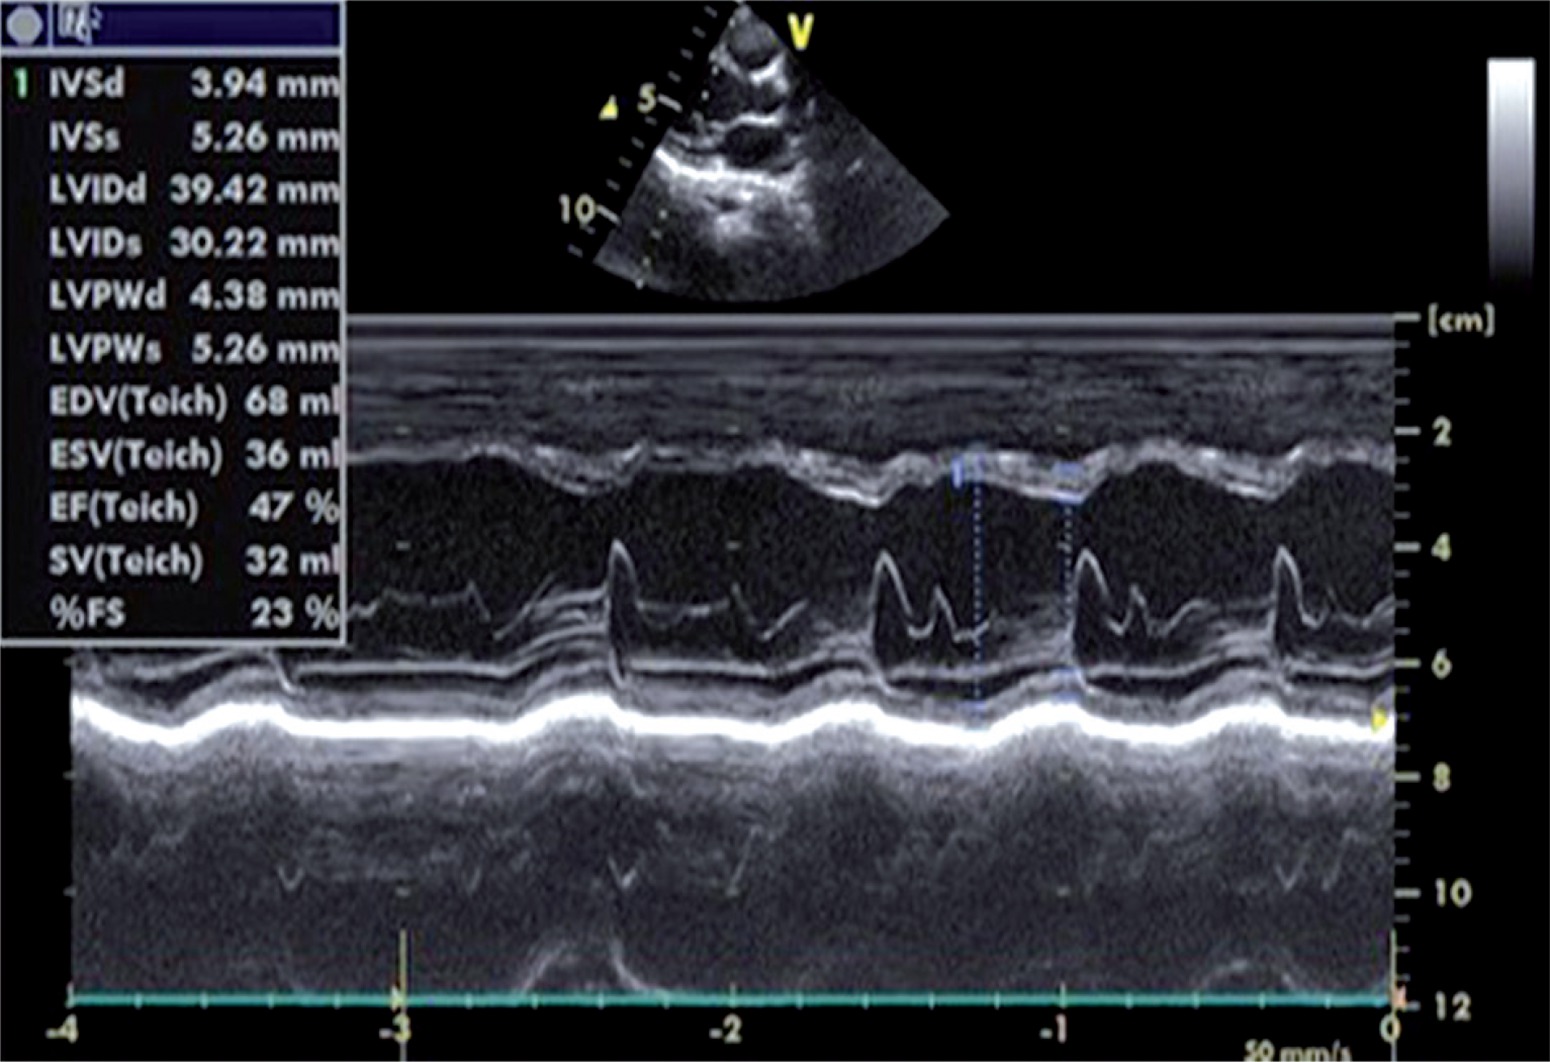

In the laboratory review of the patient the following were reported: no hepatosplenomegaly was observed, haemoglobin 12.9 gr/dl, leucocytes 14 400/mm3, thrombocytes 433 000/mm3, 30% neutrophil in peripheral spread, 12% stab neutrophil, 44% lymphocytes, 4% monocytes, 16% eosinophil, total eosinophil count 2300/mm3, AST 72 IU/l, troponin I 1.7 ng/ml (normal value: < 0.04 ng/ml), CK-MB 72 5 ng/ml, and CRP 21 mg/dl. Serological studies of Epstein-Barr virus, cytomegalovirus, human immunodeficiency virus, hepatitis A, B, and C, and mycoplasma were normal. Chest radiography was normal. Electrocardiography revealed sinus tachycardia. Table 1 shows the clinical characteristics and variables of our case. An echocardiogram revealed global hypokinesis, mild mitral regurgitation, and decreased contractility (LV ejection fraction 47%, fractional shortening 23%) consistent with the diagnosis of myocarditis (Fig. 2). A skin biopsy was performed, which demonstrated an inflammatory infiltrate that was predominantly perivascular and lymphocytic in nature (Fig. 3).

The patient was diagnosed with DRESS syndrome and secondary myocarditis, according to both the biopsy results and the RegiSCAR study group scoring system criteria in Table 2. He was treated with methylprednisolone 2 mg/kg/day and diphenhydramine 1 mg/kg i.v. q6h. After carbamazepine was discontinued and the second day of the initiation of the treatment, the clinical symptoms and the general condition improved. Eruptions were completely resolved within seven days. The patient received a total of 45 days of steroid treatment. After two months, echocardiogram showed normal cardiac contractility.